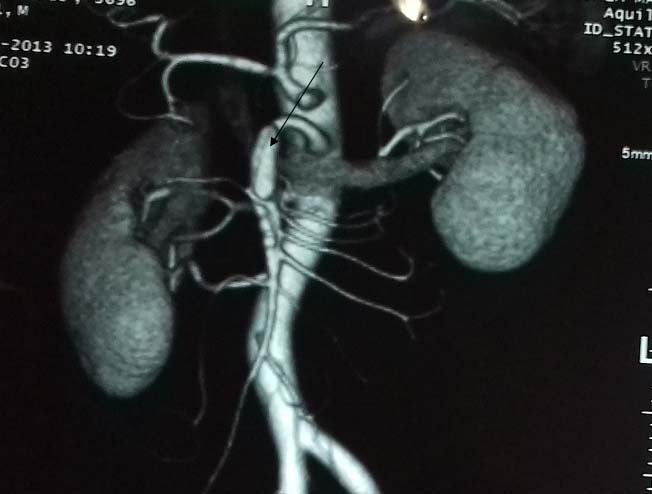

Laboratory data revealed leukocytosis with a white blood cell count of 11,000/ml. There was no evident pathology in the abdominal sonographic examination. An abdominal computed tomography scan with intravenous contrast showed a normal thoraco-abdominal aorta. However, dissection of both the celiac trunk and SMA was determined. SMA dissection was classified as Sakamoto type II b. There was no bowel oedema or free fluid. The dissection of the celiac artery was approximately 22mm long with aneurysmal dilatation [Table/Fig-1,2 and 3] with partial thrombosis causing moderate narrowing.

Abdominal CT scan with intravenous contrast (longitudinal view) reveals an isolated celiac artery dissection (arrow) measuring 22mm in length with aneurysmal dilatation.

Abdominal CT scan with IV contrast (Longitudinal view): demonstrates Celiac artery dissection.